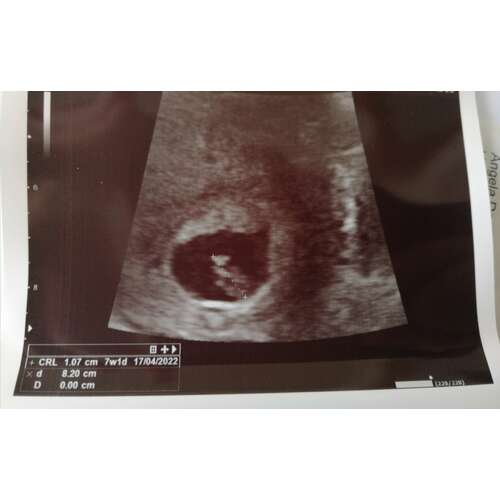

Mijn echo, denk zelf 7w6d maar meting zei 7w1d